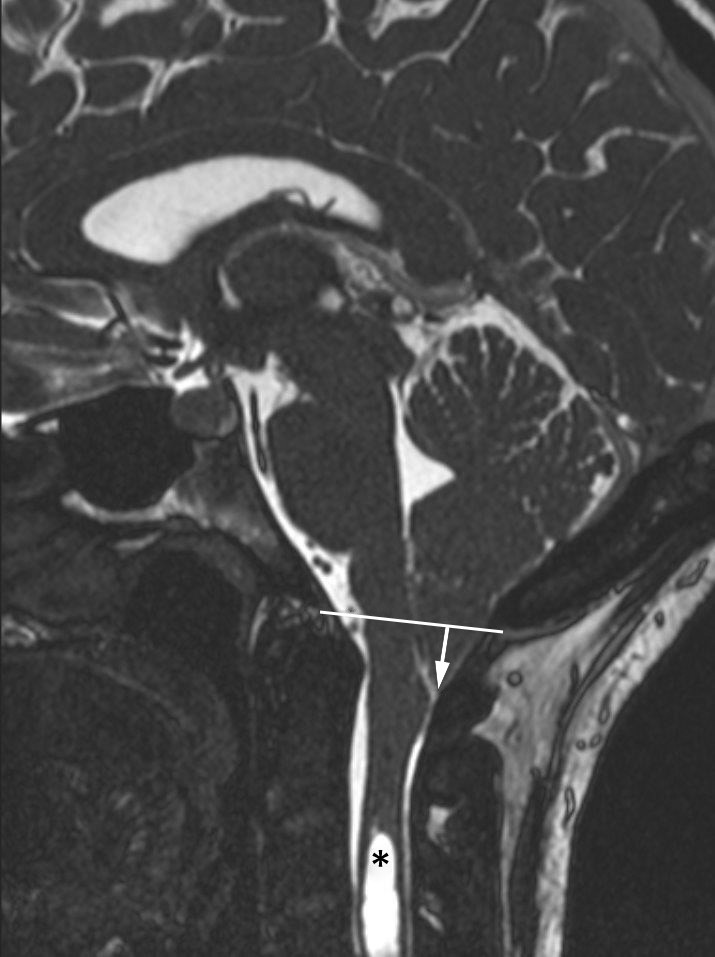

I 1890-årene beskrev den østerrikske patologen Hans Chiari (1851–1916) patologisk kaudal ektopi av lillehjernetonsiller under nivå med foramen magnum (1) (figur 1), siden kjent som Chiari-malformasjon. Det foreligger flere varianter av tilstanden (tabell 1): Type 1 skiller seg fra type 2–4 først og fremst ved at den ikke er forbundet med dysrafisme (ryggmargsbrokk), at den diagnostiseres i høyere alder (typisk eldre barn og unge voksne) og at ektopien gjelder kun lillehjernetonsiller. Ektopi av nervestrukturer i bakre skallegrop og eventuell syringomyeli er felles for alle typer, men ellers fremstår type 1 klinisk og radiologisk som en distinkt entitet. Såkalt type 0 benyttes om en idiopatisk syringomyeli uten bakenforliggende funn av cerebellær ektopi eller annen åpenbar forklaring (som intramedullær svulst eller ryggmargsskade). Betegnelsen type 1.5 benyttes om type 1 med enkelte anatomiske/radiologiske trekk som ellers er typiske for type 2, men uten dysrafisme.

Ryggmargstjoring er en kjent mekanisme ved Chiari-malformasjon type 2, der denne er til stede grunnet medfødt ryggmargsbrokk, typisk lumbosakralt. Under lengdevekst av ryggraden strekkes den tjorede ryggmargen, noe som i sin tur strekker nervestrukturer i bakre skallegrop ned gjennom foramen magnum. Når denne mekanismen knyttes til Chiari-malformasjon type 1, antas det å foreligge en okkult, moderat variasjon av spinal dysrafisme (10). Dette er imidlertid meget sjelden tilfelle. Funn som eventuelt indikerer ryggmargstjoring, for eksempel et fibrolipom i filum terminale (figur 2), kan langt på vei utelukkes ved MR av columna. Teorier om ryggmargstjoring som en eksklusiv bakenforliggende årsak til type 1-malformasjon er lite berettiget, og også denne mekanismen er sannsynligvis aktuell kun hos liten andel av pasientene (10).

Chiari-malformasjon type 1 diagnostiseres ofte tilfeldig hos pasienter henvist til MR av ulike årsaker. Påvisningens betydning for symptomer som kan relateres til tilstanden, bør avklares med nevrolog. Som MR-kriterium for diagnosen skal det påvises ektopi av lillehjernetonsiller > 5 mm under nivå med foramen magnum, definert av en linje mellom basion og opisthion (figur 1).

Norske medier har nylig omtalt kirurgisk behandling av Chiari-malformasjon type 1 på en klinikk i utlandet, der flere norske pasienter har blitt behandlet. Etter det vi erfarer, består denne behandlingen av kirurgisk klipping av filum terminale, en tynn streng av fibrøst vev longitudinelt forløpende mellom conus medullaris og nedre del av duralsekken. Denne strukturen har ingen fysiologisk funksjon, men kan i visse tilfeller ligge såpass festet kaudalt i spinalkanalen at det forårsaker stramming av ryggmargen. Denne tjoringen er en vanlig problemstilling hos barn med medfødt ryggmargsbrokk og Chiari-malformasjon type 2 og/eller intraspinale lumbosakrale lipomer, eventuelt assosiert med et smalt fibrolipom i filum terminale (fatty filum) figur 2). I barnenevrokirurgisk praksis er klipping av filum terminale et relativt vanlig inngrep, men det er meget sjelden indisert hos voksne pasienter med Chiari-malformasjon type 1, unntatt hos en liten undergruppe med tjoring (adult tethered cord syndrome) ((10).